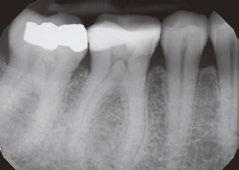

Figures 3A-3H: 3A. Preoperative periapical radiograph of tooth No.10 showing internal root resorption in apical third of root. There is significant alveolar bone loss adjacent to defect. 3B. Sagittal CBCT image of tooth No. 10 showing internal resorptive defect perforating on mesial aspect of root. Note adjacent alveolar bone loss extending proximally to tooth No. 9. 3C. Axial CBCT image of internal resorptive defect perforating on mesial aspect of root. There is thin layer of circumferential dentin remaining and extensive alveolar bone loss adjacent to the defect. 3D. Periapical radiograph showing gutta-percha cone fit. Gutta-percha cone passes through resorptive defect to contact apical portion of root canal. 2E. Immediate postoperative periapical radiograph of tooth No.10 once root canal was completed and resorptive defect was restored. 2F. Two-year follow-up showing complete healing of radiolucency adjacent to defect and reestablishment of PDL. 2G. Two-year follow-up CBCT. Coronal slice showing complete healing of radiolucency adjacent to defect and reestablishment of PDL. 2H. Five-year follow-up radiograph. Patient is completely asymptomatic

A 41-year-old male presented with a chief complaint of pain and swelling adjacent to tooth No. 10. The patient reported a history of trauma as a teenager, though he had not experienced issues until the recent onset of pain and swelling. Clinical examination revealed tenderness on the buccal gingiva around tooth No. 10, with sensitivity to percussion and biting. A small, fluctuant intraoral swelling was noted near the apex of tooth No. 10, and the tooth did not respond to vitality testing. Radiographic examination showed a large perforating internal resorptive defect near the apical third of the root (Figure 3A). CBCT (Veraviewepocs 3D R100; J. Morita) revealed significant alveolar bone loss adjacent to the defect, extending along the entire mesial side of

the apical half of the root of tooth No.10 and reaching the root of tooth No. 9 (Figures 3B and 3C).

A diagnosis of pulpal necrosis with acute apical abscess was made. All treatment options, including extraction with replacement by an implant or bridge, were discussed. The patient, motivated to retain the tooth, opted for root canal therapy and repair of the resorptive defect. Informed consent was obtained.

First visit

The patient was anesthetized with 1.7 mL of 4% articaine with 1:100,000 epinephrine (Septocaine®; Septodont®, Lancaster, Pennsylvania) via labial infiltration. Rubber dam isolation was achieved, and the tooth was accessed using a No. 2 surgical length carbide round bur. Necrotic pulp was encountered. Working length was established with a Root ZX® apex locator (Morita, Tokyo, Japan), and the canal was instrumented to a size 35 .04 Vortex Blue® rotary file (Dentsply Tulsa Dental, Johnson City, Tennessee). Care was taken to ensure that the files passed through the resorptive defect and entered the apical portion of the canal. The canal was irrigated with 5.25% sodium hypochlorite, and the EndoActivator® (Dentsply, Tulsa, Oklahoma) was used to sonically agitate the irrigant to promote thorough disinfection of the resorptive defect. The canal was dried with paper points, and calcium hydroxide (Ultracal™ XS, Ultradent Products Inc, South Jordan, Utah) was syringed into the canal and the defect. The tooth was then temporarily restored with Cavit® (3M ESPE, Neuss, Germany).

Second visit

Two weeks later, the patient returned for completion of the endodontic treatment, reporting that all symptoms had subsided. Clinical examination confirmed that the swelling had resolved. Calcium hydroxide was removed from the canal through instrumentation, irrigation, and activation with the EndoActivator. The canal was dried with paper points, and excess irrigant was removed using surgical suction with a micro-tip. A master gutta-percha cone was placed to the working length and confirmed with radiographic examination (Figure 3D). The canal was coated with EndoSequence® BC (bioceramic) sealer (Brasseler USA, Savannah, Georgia) to ensure sufficient sealer filled the resorptive defect. It was then obturated with gutta percha and BC sealer using the technique of warm vertical condensation (Figure 3E). The lingual access opening was restored with TPH Spectra® ST composite (Dentsply Sirona, Charlotte, North Carolina), and the patient was scheduled for recall to monitor healing.

At 1-year, 2-year, and 5-year recall visits, the patient was asymptomatic, and radiographs showed complete healing with full restoration of bone and lamina dura adjacent to the resorptive defect (Figures 3F and 3H). The patient expressed satisfaction with the outcome, having retained a tooth originally planned for extraction.